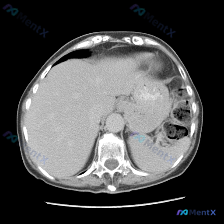

这是一张腹部CT软组织窗横断面图像。

跳开预设再全片扫一遍,马上发现了问题——在肝脏前缘和腹壁之间,有一个非常典型的「新月形」低密度影(黑色区域),这是气体密度。

这就是「游离气腹」,也叫气腹,是腹腔内空腔脏器穿孔的直接影像学证据。